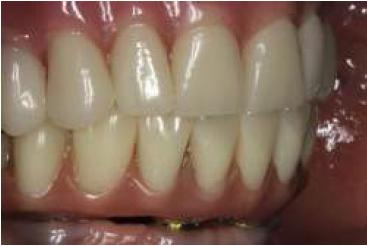

Al tercer día se realizó la instalación con torque manual y ajuste oclusal (figs. 13,14,15,16).

A los 10 días, luego de la cirugía, se citó a la paciente a control para realizar la retirada de la sutura11; se dio torque a los tornillos protésicos (10 N/cm) y se chequeó la oclusión nuevamente. Se ha seguido controlando a la paciente cada 6 meses, hasta cumplir 2 años desde la fecha de instalación de la aparatología, sin manifestar complicación alguna (figs. 17, 18, 19, 20, 21).

Se puede observar un control adecuado de biofilm por parte de la paciente.